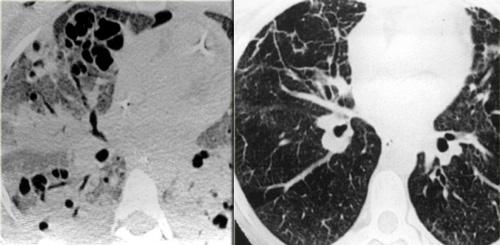

Bên trái là mô bào tế bào Langerhans giai đoạn sớm với các nốt nhỏ.

Không có nang nào được nhìn thấy.

Mô bào tế bào Langerhans giai đoạn muộn. Các nang tiến triển thành nang hình dạng bất thường điển hình.

Ở giai đoạn muộn hơn, các nốt bắt đầu hoại tử tạo hang và trở thành nang.

Các nang này ban đầu có dạng hình tròn nhưng cuối cùng hợp lại tạo thành các nang hình dạng bất thường điển hình của LCH.